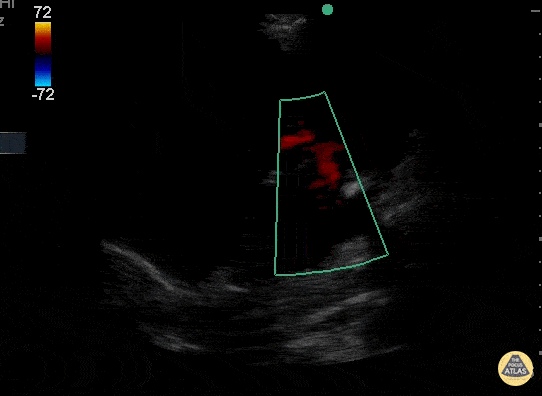

Valvulopathy - Moderate Mitral Regurgitation

A mitral regurgitant jet is seen in this apical 4-chamber view that appears to be ~35-40% the area of the left atrium. This is most consistent with moderate MR though a more quantitative method such as PISA can be used for formal evaluation. Jason Tanguay, DO